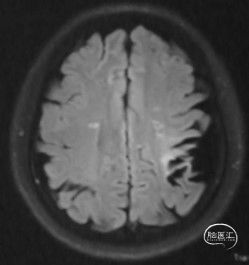

病人甲的影像资料:

T2 Flair:左侧额顶叶脑软化灶,右侧内分水岭区腔梗;

弥散:阴性;